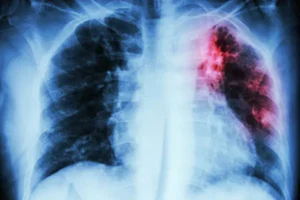

Lao phổi là bệnh truyền nhiễm do vi khuẩn Mycobacterium tuberculosis gây ra, tấn công chủ yếu vào phổi nhưng cũng có thể lan sang các cơ quan khác. Bệnh lây qua đường hô hấp khi người bệnh ho, hắt hơi hoặc nói chuyện.